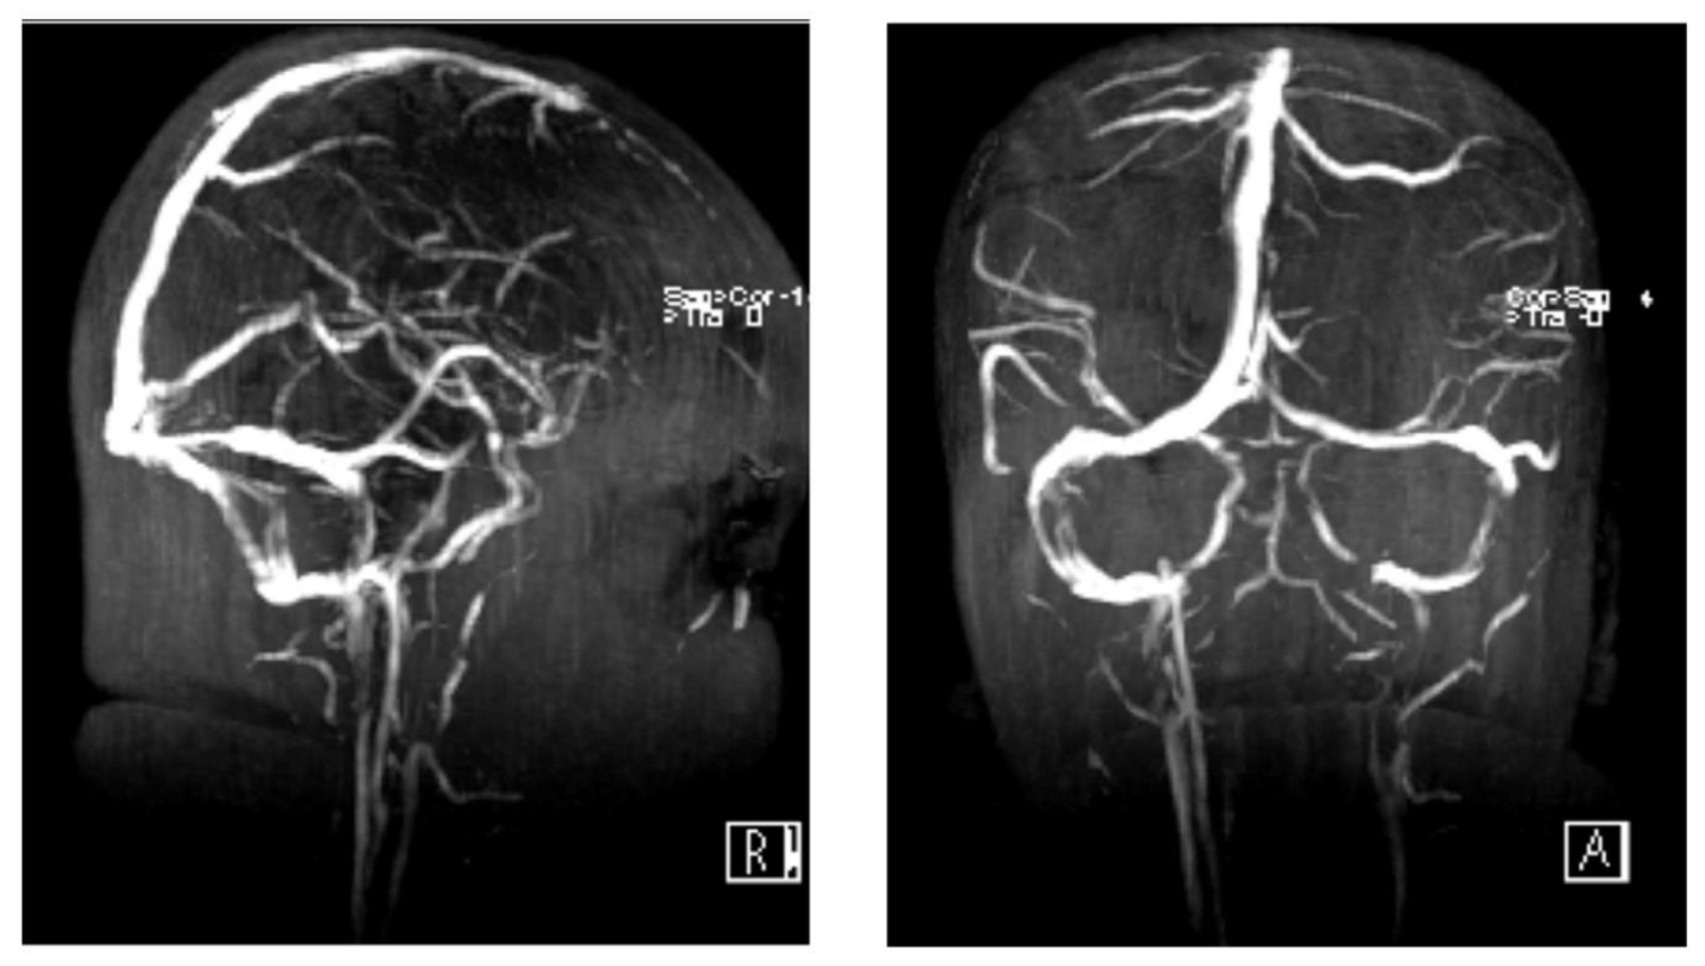

2. Case Presentation